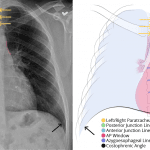

- Widening of the superior mediastinum, which also has an abnormal convex contour

- Acute right posterior third through ninth fractures

- Patchy right infrahilar opacity

- No pleural effusion or pneumothorax

Widening of the superior mediastinum, which also has an abnormal convex contour. Findings are concerning for hematoma or aortic injury in the context of trauma. Recommend chest CTA for further evaluation.

Patchy right infrahilar opacity may reflect atelectasis, contusion, or aspiration in the setting of trauma.

Acute right posterior third through ninth rib fractures. No pneumothorax or pleural fluid collection.